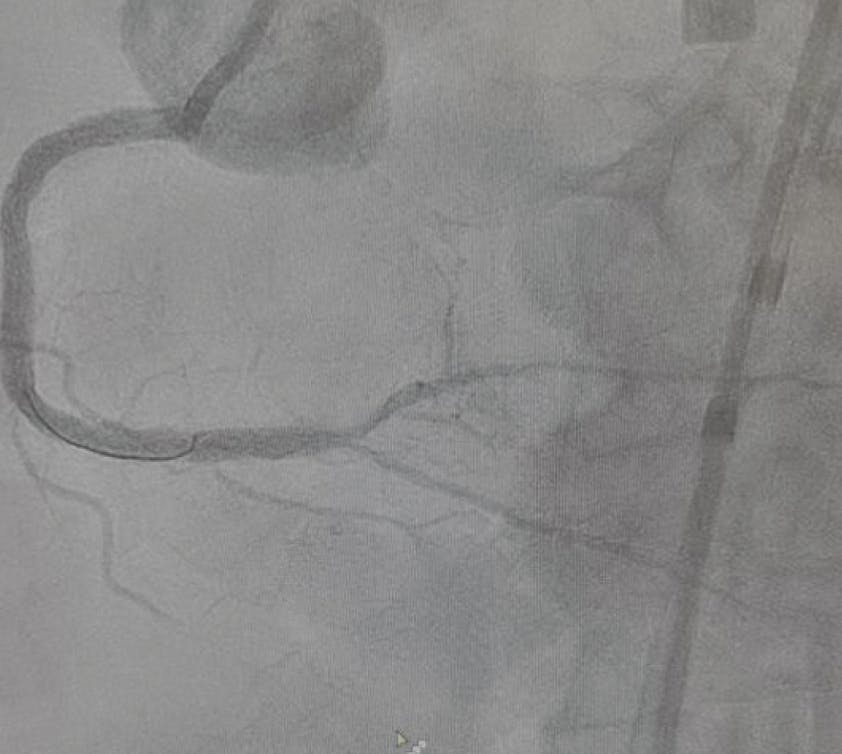

Figure 2. Dual angiography of a dominant RCA CTO showing a functional CTO of the proximal RCA vessel with a short-segment (< 20 mm) CTO of the distal RCA, with an unambiguous proximal cap, reasonable distal landing zone, and difficult retrograde collaterals (A). Successful wiring into the R-PLV branch (B).

Using an 8-F Trapliner (Teleflex) in the AR guide, we took a 135-cm Corsair Pro microcatheter (Asahi Intecc) and a Runthrough wire (Terumo Interventional Systems) to the proximal cap of the RCA CTO and crossed the proximal and distal segments of the CTO with a Mongo jacketed wire (Asahi Intecc) with the wire going into the true lumen of the right posterolateral ventricular (R-PLV) branch, noted in multiple views on retrograde angiography (Figure 2B).

Unfortunately, the microcatheter would not cross the distal cap of the CTO, nor would a 1.5-mm semicompliant balloon, despite advancement of the guide extension. Given how close the microcatheter was able to get to the distal cap, we removed the Mongo wire and free-wired back into the R-PLV branch with a modified Rotofloppy wire (Boston Scientific Corporation) that had the radiopaque 0.014-inch segment cut short to facilitate wiring (Figure 3). We then performed rotational atherectomy of the CTO segment with a 1.5-mm burr over two 30-second runs, with the burr crossing the distal cap on the second run. The burr was removed and we used the microcatheter to switch the Rotofloppy wire out for the Runthrough wire. We then predilated the lesion with a 2.0-mm semicompliant balloon followed by a 2.5-mm NC balloon at nominal pressure with good expansion. Intravascular ultrasound (IVUS) was performed, showing some calcium fractures in the distal RCA but with residual concentric rings of thick calcium in the mid and proximal RCA (Figure 4).